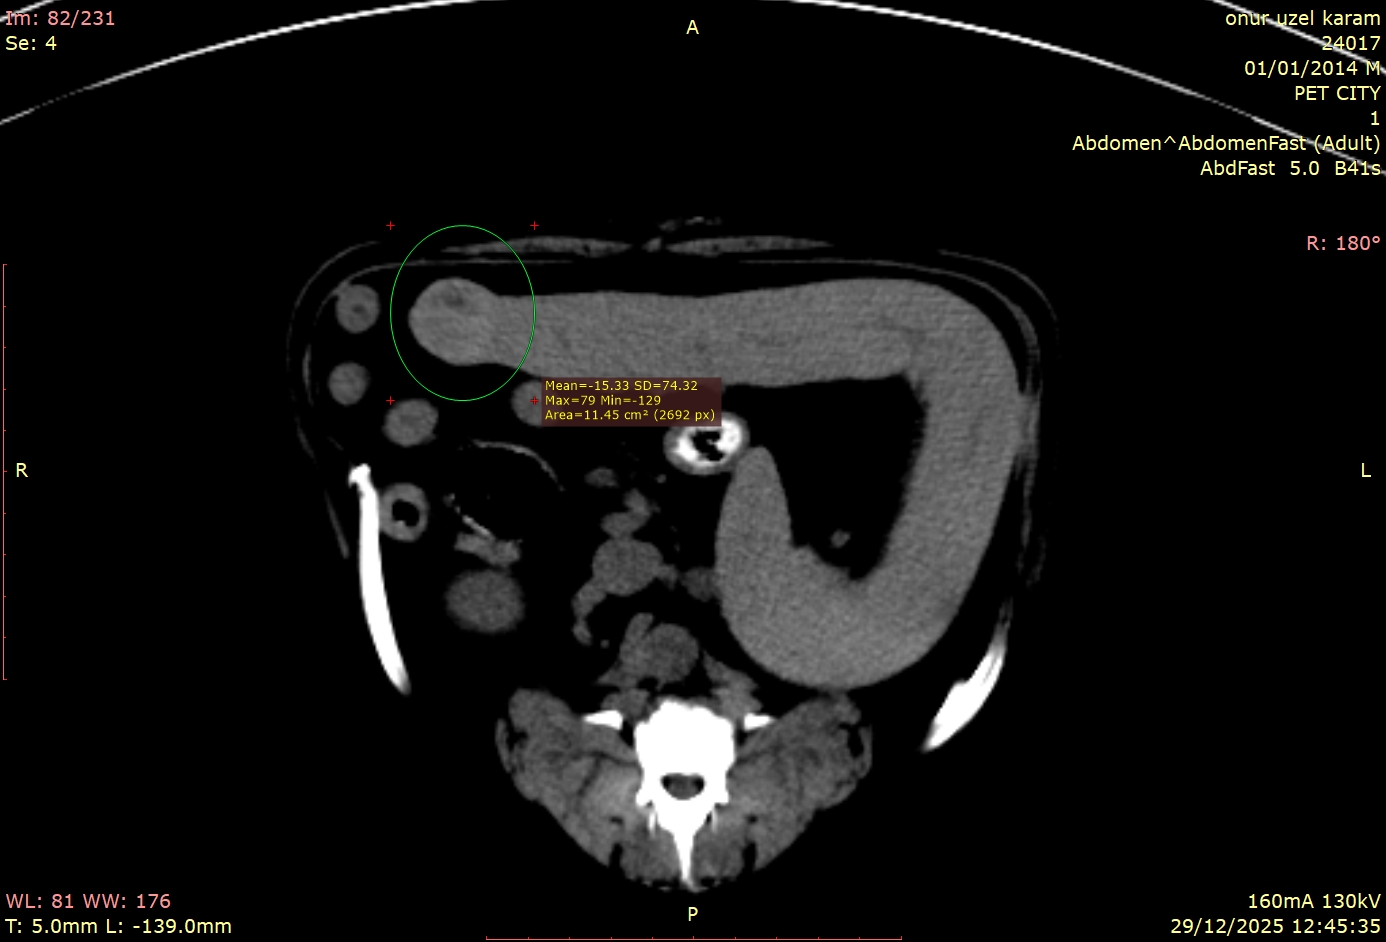

Hastamızın tomografi görüntülerini incelediğimizde, bizi şaşırtan ve tedavi planımızı kökten etkileyen detaylarla karşılaştık:

Bu vakadaki en kritik nokta, dalaktaki kitlenin tamamen "sessiz" olmasıydı. Hasta sahibinin fark edebileceği hiçbir semptom yoktu. Eğer sadece prostata odaklanıp ileri görüntüleme tekniklerini kullanmasaydık, dalaktaki bu lezyon gözden kaçabilirdi.

Tomografi çekilmemiş olsaydı, bu kitle belki de çok daha ileri bir evrede, tedavi şansının azaldığı bir dönemde karşımıza çıkacaktı. Bu vaka, tomografinin yalnızca mevcut problemi çözmekle kalmayıp, henüz belirti vermeyen gizli tehlikeleri de erken dönemde yakalama gücünü net bir şekilde göstermektedir.